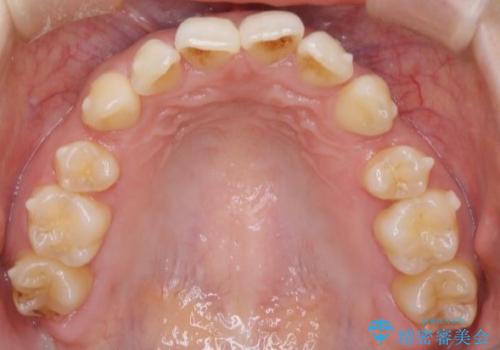

- 患者様は、上下の噛み合わせのバランスが悪く、特に上顎の前歯の突出を気にされて来院されました。診査の結果、下顎の歯並びに合わせて上顎を後方へ移動させる必要があると判断し、上顎の小臼歯2本を抜歯することを提案しました。目立たない矯正を希望されたため、**インビザライン(マウスピース矯正)**を選択。計画的にスペースを作りながら、バランスの取れた歯並びを目指しました。

治療はまず、上顎の小臼歯を2本抜歯し、そのスペースを利用して前歯を後方へ移動させました。インビザラインはアタッチメントを併用し、より効率的に歯を動かせるよう調整。定期的なチェックとアライナーの交換を続け、約3年かけて理想的な歯並びと噛み合わせを実現しました。治療後はリテーナーを使用し、安定した状態を維持。患者様からは「口元がスッキリし、横顔の印象も変わった」と嬉しいお声をいただきました。